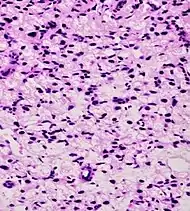

| Signet-ring adenocarcinoma | 0.02%[16] | ![]() |

|

Tumorous glands: | Not recommended[1] | ||